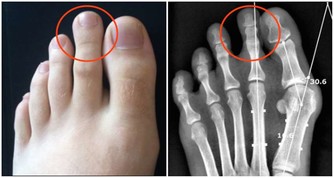

足癬是一種接觸傳染性皮膚病。如果接觸了帶真菌的腳、鞋襪、拖鞋、毛巾和水等,真菌數量比較多,毒力比較強,接觸者的皮膚又比較潮濕,就容易被傳染。